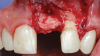

(3.) The crown was removed, and a partial thickness flap was reflected using a papilla-sparing incision design, which revealed that the implant was positioned too far facially and that its body was visible through a very thin layer of bone.

Figure 3

(4.) The crown was removed, and a partial thickness flap was reflected using a papilla-sparing incision design, which revealed that the implant was positioned too far facially and that its body was visible through a very thin layer of bone.

Figure 4

The patient in this case had undergone implant therapy at the site of tooth No. 9 and was restored with a cement-retained restoration more than 5 years prior. At presentation, the site demonstrated a peri-implant soft-tissue dehiscence that extended approximately 3-mm apical to the gingival margin of tooth No. 8. Thin and erythematous marginal tissue was evident at the zenith (Figure 2). The crown was removed, and a partial thickness flap was reflected using a papilla-sparing incision design. This revealed that the implant was positioned too far facially and that its body was visible through a very thin layer of bone (Figure 3 and Figure 4). The first objective of treatment was to minimize the facial extent of the emerging abutment and crown. To accomplish this, the facially positioned abutment and implant crown margin were both recontoured. The second treatment objective was to provide additional supracrestal soft tissue that would more adequately maintain the peri-implant margin. The tuberosity was selected as a donor site due to its dense, high-quality connective tissue, low propensity for shrinkage, and association with minimal patient discomfort. Once the graft was secured (Figure 5 through Figure 7), the flap was coronally positioned (Figure 8). After a healing period of 2 weeks, the margin of tooth No. 9 exhibited an ideal position in relation to its contralateral counterpart and demonstrated increased soft tissue thickness (Figure 9). Three months postoperatively, further healing had improved the esthetics and the position of the margin had been maintained (Figure 10).